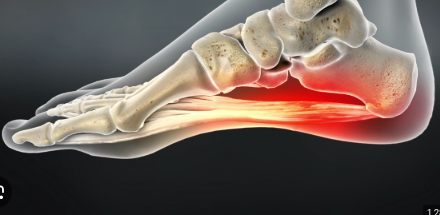

Plantar fasciitis mechanism (4)

Overuse, overweight, pregnant, improper footwear

Plantar fasciitis

Pain in bottom of foot by heel, pain decrease as foot warms, pain increases with standing/ PF

Heel spur treatment

Ice, NSAIDs, orthotics, night splints, stretching plantar fascia, cortisone shots, surgery

Night splint

Device that keeps plantar fascia in stretched position